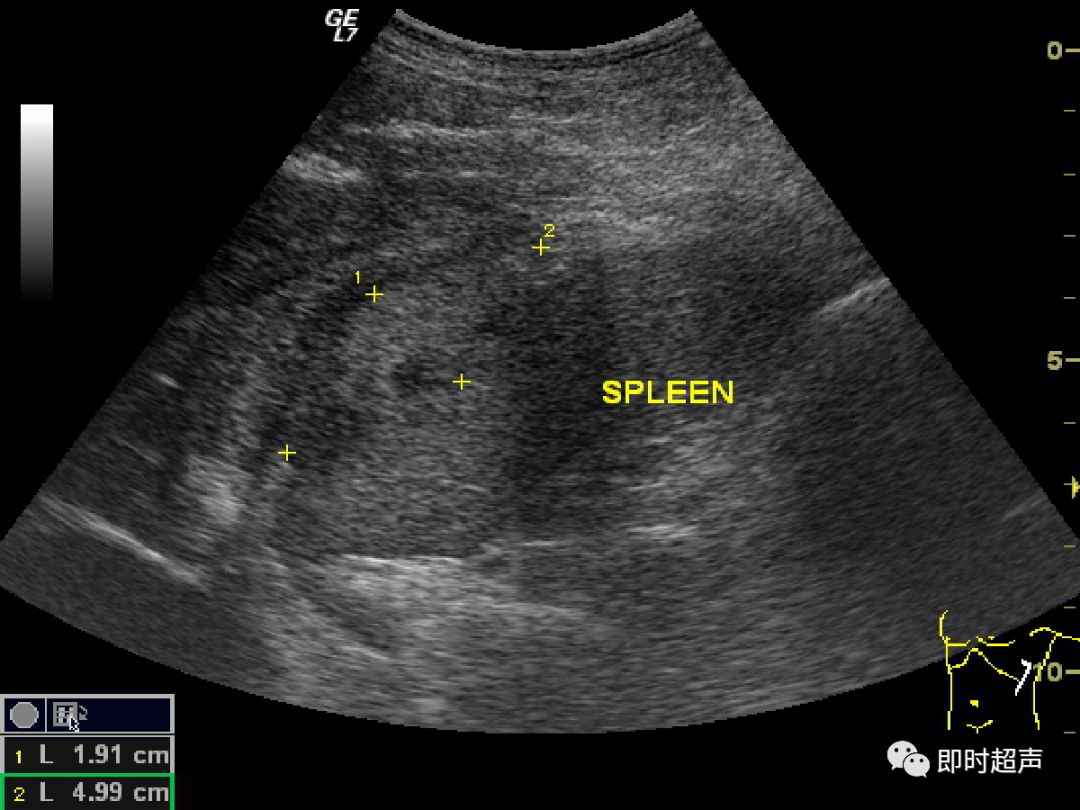

内脏反转超声报告

内脏反转超声报告,内脏反位超声报告模板